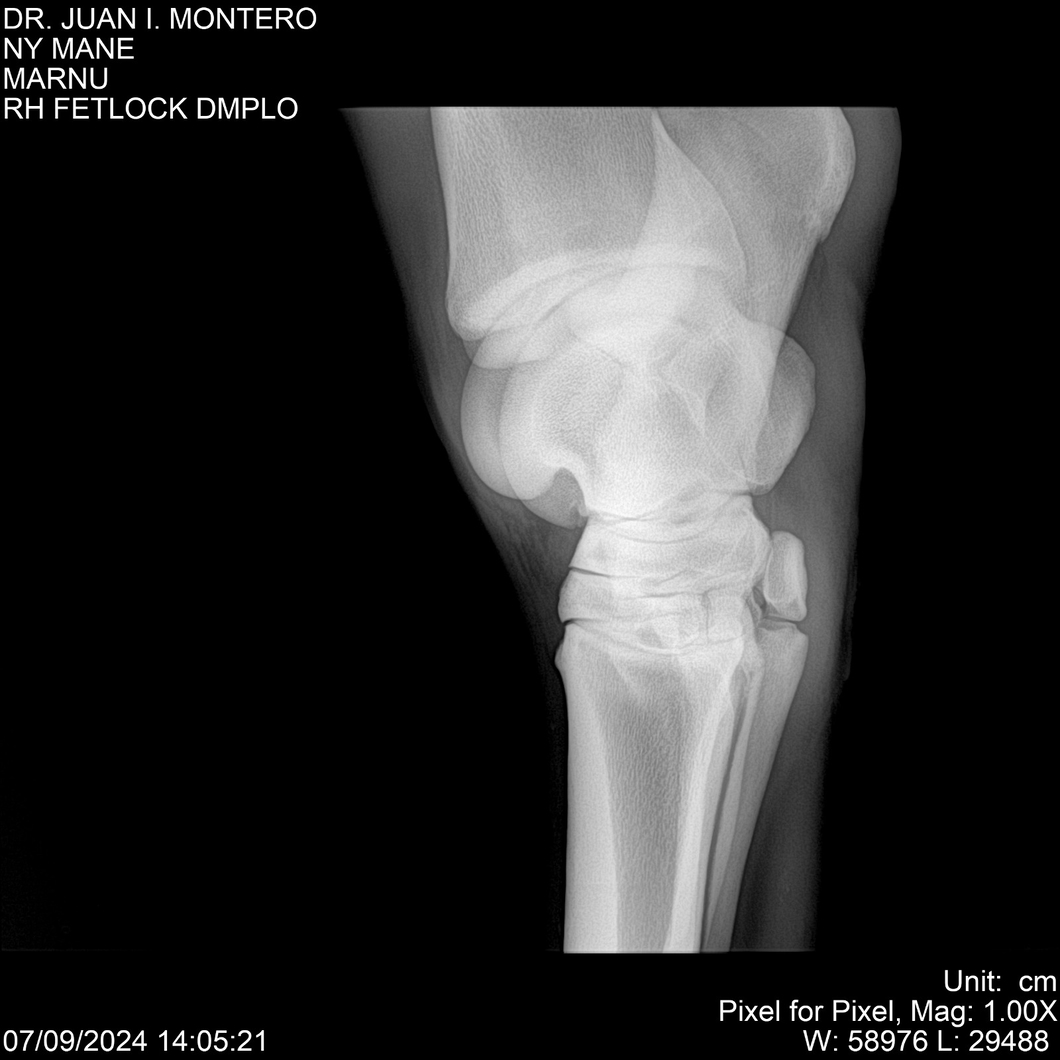

LOTE 20, NY MANE Lote Anterior Volver al remate Lote Siguiente Ficha Contacto Montevideo - Ficha del Lote Identificador: #282520 Categoría: Yeguarizos 76 Visualizaciones ClicData Contacto Empresa: Abelenda N. R., Walter Hugo Nombre*: Teléfono* : E-mail* : Mensaje Enviar Registrese gratis Este contenido Exclusivo está disponible sólo para usuarios registrados Ingresar